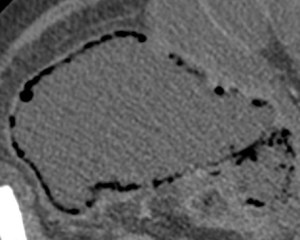

5º) Neumatosis intestinal y portal. Aire extraluminal.

Son signos poco frecuentes pero muy específicos de isquemia intestinal, E cercana al 100%. Se obsevan mejor en el TC SIN contraste.

La neumatosis intestinal consiste en aire localizado en la pared del intestino. Se produce por discontinuidad de la pared con paso de aire hacia las capas más externas y a las venas intramurales.

La presencia de neumatosis portal y mesentérica consiste en pequeñas burbujas de gas dentro de los vasos mesentéricos o que también pueden extenderse hacia las ramas intrahepáticas de la vena porta, encontrándose típicamente en la periferia del hígado.